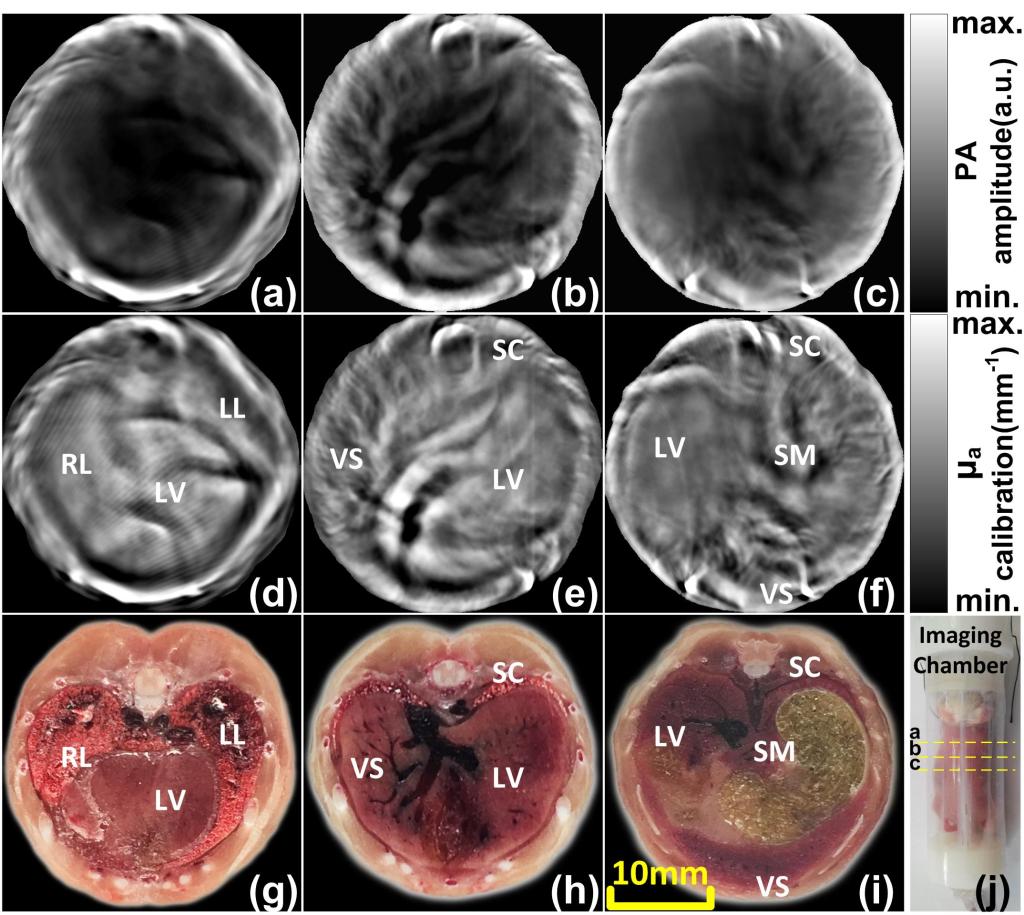

图4 活体小鼠在体实验:(a)-(c)多入射角度c-PAT重建结果((j)中黄虚线所示层);(d)-(f)多入射角度q-PAT重建结果((j)中黄虚线所示层);(g)-(i)所选成像层对应的冷冻切片结果;(j)活体小鼠与成像腔实物图